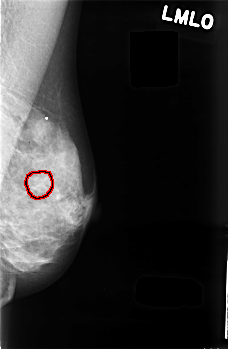

C_0482_1.LEFT_MLO

LEFT_MLO LINES 4536 PIXELS_PER_LINE 2952 BITS_PER_PIXEL 12 RESOLUTION 50 OVERLAY

FILE: C_0482_1.LEFT_MLO.OVERLAY

TOTAL_ABNORMALITIES 1

ABNORMALITY 1

LESION_TYPE CALCIFICATION TYPE AMORPHOUS DISTRIBUTION CLUSTERED

ASSESSMENT 4

SUBTLETY 2

PATHOLOGY BENIGN

TOTAL_OUTLINES 1

BOUNDARY